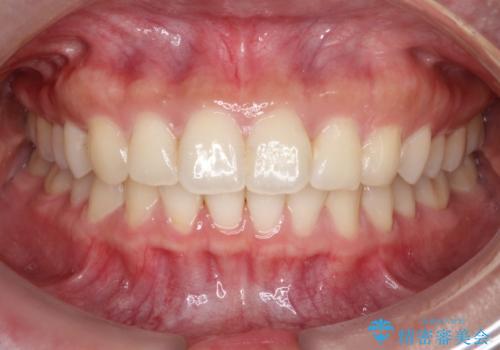

- 前歯の捻れと口元の突出を主訴に来院されました。

インビザラインを用いて上顎の遠心移動を行い、前歯を下げながら凸凹を綺麗に治すことができました。

歯を抜かない矯正治療を行う場合、口元は極端には変わりません。

今回は奥歯の遠心移動を行い、できる限り前歯を下げられるように治療を行いました。